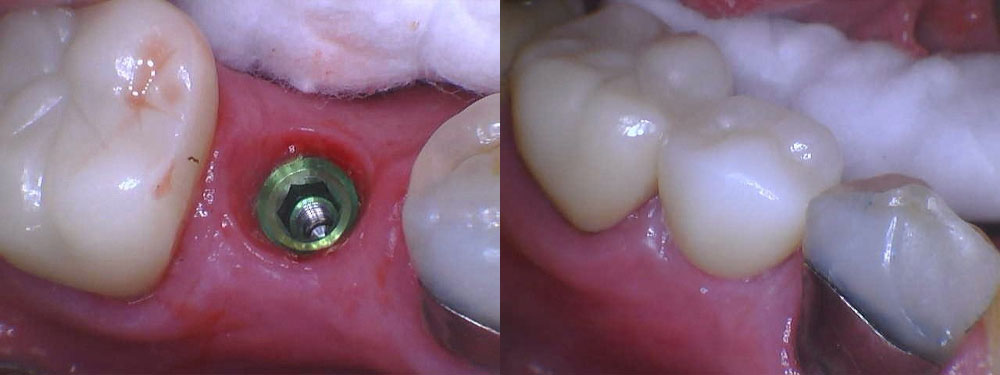

- Implant Placement: The dental implant placement procedure is performed under local anesthesia for your comfort. Dr. Cordora will carefully place the titanium implant posts into the jawbone at precise angles and depths to ensure the stability and strength of each implant.

- Healing Period: After implant placement, a healing period of several months is required to allow the implants to integrate with the surrounding bone. During this time, temporary restorations may be placed to maintain aesthetics and function.

- Final Restoration: Once the implants have fully healed and integrated with the jawbone, custom-made dental crowns, bridges, or dentures are securely attached to the implants, completing your smile restoration.